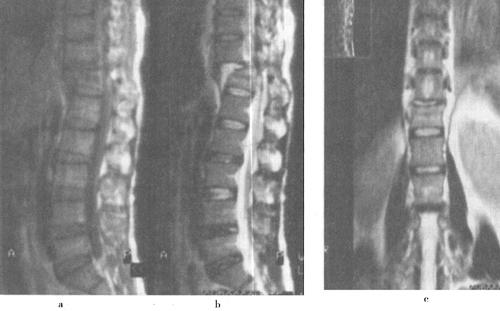

(2)脊髓软化和空洞:脊髓软化在创伤后48h后即可开始,是由于脊髓内出血、水肿引起的炎症性反应和肉芽组织对创伤组织的清除所致,可能同时伴有胶质细胞的增生和吞噬细胞功能的增强使脊髓脂质崩解、软化和液化,并被吞噬细胞吞噬和转移,最终形成脊髓软化和空洞形成。MRI可显示这种病理改变。脊髓软化灶在T1WI表现为低信号,在T2WI为高信号,增强扫描无强化。脊髓空洞在T1WI和T2WI信号等同于脑脊液信号,而边缘更加清晰(图7-19)。脊髓软化和空洞是神经系统症状恶化的主要原因。脊髓空洞引流是治疗的重要手段,因而正确的诊断和定位十分重要。大约9%~20%的脊髓损伤病人可出现脊髓空洞症。

图7-19 脊髓创伤后脊髓软化:MRI、T1WI和T2WI矢状面显示C5水平颈髓内可见一长条状异常信号影,T1W低信号,T2W高信号,类似脑脊液信号,为创伤后软化灶

(3)创伤性蛛网膜囊肿:创伤性蛛网膜囊肿是由于脊柱创伤引起脊膜撕裂脑脊液外漏积聚造成,可对脊髓造成压迫性改变。囊肿在T1WI、T2WI呈脑脊液样信号,边界清楚,呈单囊或多囊状改变(图7-20)。

图7-20 脊柱创伤后脊膜囊肿:囊肿在T1WT呈低信号,在T2WI呈高信号,类似脑脊液信号,该节段脊髓圆锥和马尾神经明显受压迫移位,椎体和附件骨质受压吸收